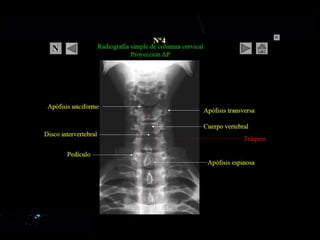

Columna vertebral

• La columna vertebral esta

• 7 cervicales: atlas, axis, 5 vc

• 12 torácicas

• 5 lumbares

• 5 sacras

• 3-4 coccígeas (varia)

CERVICALES

Generalidades • La columnavertebral esta formada por: • 7 cervicales: atlas, axis, 5 vc • 12 torácicas • 5 lumbares • 5 sacras • 3-4 coccígeas (varia)